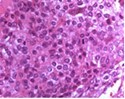

Figure 2.Chondroblastoma delineating aggregates of polyhedral chondroblastic cells with angulated, abundant, eosinophilic cytoplasm and vesicular nuclei enmeshed within a chondomyxomatous matrix6.

Chondroblastoma delineating aggregates of polyhedral chondroblastic cells with angulated, abundant, eosinophilic cytoplasm and vesicular nuclei enmeshed within a chondomyxomatous matrix6.

Upon microscopy, tumefaction is significantly cellular and composed of sheets of spherical to polyhedral chondroblastic cells imbued with abundant, eosinophilic cytoplasm and well demarcated cellular perimeter. Intracytoplasmic glycogen granules are evident. Nuclei appear elliptical, hyper-lobulated and demonstrate nuclear grooves. Nuclear atypia appears insignificant 1, 2.

Focal aggregates of spindle-shaped cells may be enunciated. Peri-cellular zones of ‘lace-like’ or ‘chicken wire’ calcification appear intermingled with degenerative chondroblasts. Eosinophilic foci of chondroid matrix are invariably discerned 1, 2.

Focal mitotic activity, necrosis and osteoclast-like giant cells may be commingled with cellular zones. Besides, aneurysmal bone cyst-like modifications are commonly observed 1, 2.